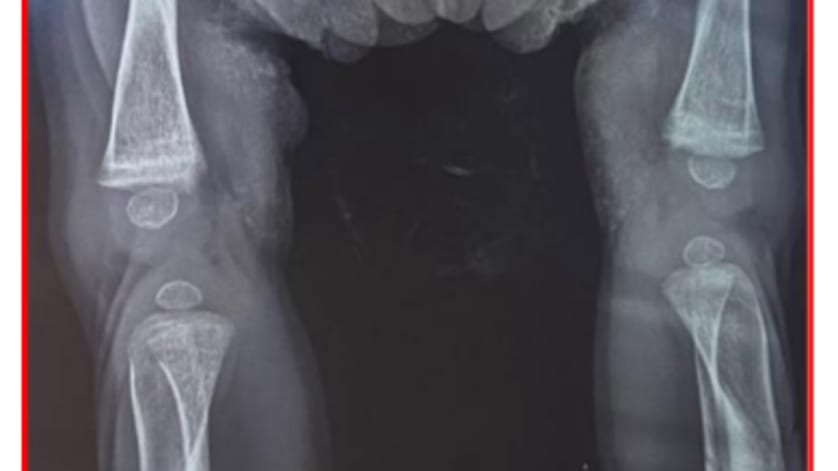

February 10, 2026 Novel LIFR Variant Identified in Stuve-Wiedemann Syndrome Case report highlights the role of early genetic confirmation in severe skeletal dysplasia Conexiant